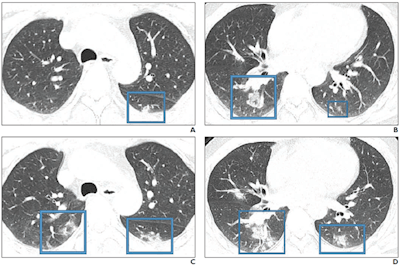

47-year-old Chinese man with two-day history of fever, chills, productive cough, sneezing, and fatigue who presented to the emergency department. A and B: Initial CT images obtained show small round areas of mixed ground-glass opacity and consolidation (rectangles) at level of aortic arch (A) and ventricles (B) in right and left lower lobe posterior zones. C and D: Follow-up CT images obtained two days later show progression of abnormalities (rectangles) at the level of aortic arch (C) and ventricles (D), which now involve right upper and right and left lower lobe posterior zones. Images courtesy of the American Journal of Roentgenology.

"An investigation of initial chest CT findings in 21 individuals with confirmed COVID-19 reported abnormal findings in 86% of patients, with a majority having bilateral lung involvement," the authors wrote.